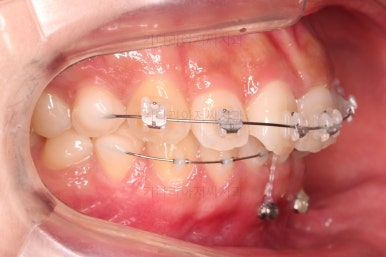

아래 앞니는 브라켓보다는 훨씬 작은 미니튜브 장치를 사용했습니다.

과개교합의 경우 브라켓을 부착하게 되면 씹히게 되어 치료과정이 수월하지 못하기 때문이죠.

중간중간 미니스크류가 빠지든, 위치적으로 좋은 곳을 선택하든 여러 이유로 미니스크류 재식립이 몇 번 있었고요.

부족한 공간은 치간삭제를 통해서 만들어 나갑니다.

디테일을 위해서 윗니는 어금니에도 하나씩 장치를 더 부착했고, 아랫니는 바로 뒷 치아에도 장치를 부착했습니다.

과개교합 개선에 미니스크류까지 사용되었던 터라 매우 난이도가 높은(전체교정보다 훨씬 난이도가 높습니다.) 부산앞니부분교정이어서 1년여의 기간이 걸렸는데요.

기왕(부분교정임을 감안했을 때) 오래 걸린거 좀 더 완성도를 높이고자 아래 앞니는 설측교정까지 부착했습니다.

역시 미니튜브 장치를 이용했고, 아래 앞니 안쪽에다가 장치를 부착해서 아주 미세한 배열을 맞춰드렸습니다.